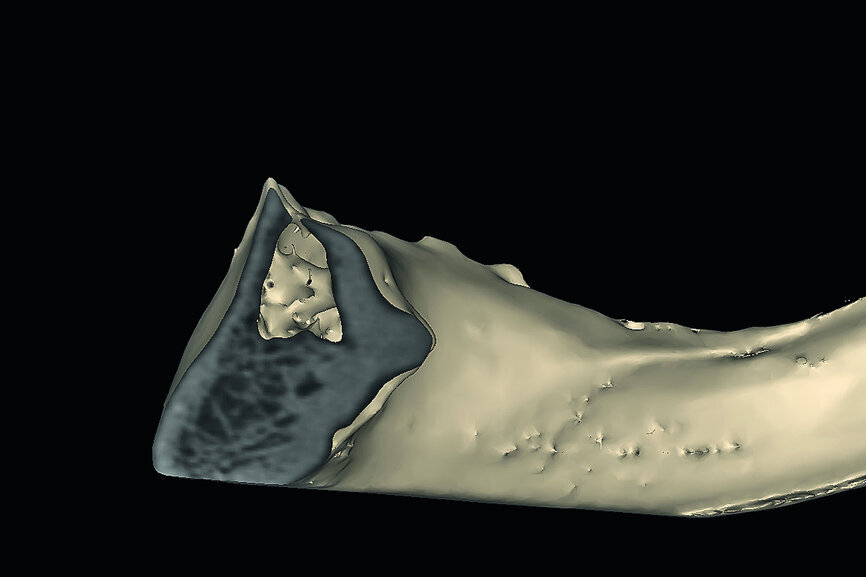

Fig. 3: Cross-sectional slice revealing the trajectory of the maxillary alveolus vs the trajectory of the root when planning for an implant.

A 74-year-old male presented to the clinic with a chief complaint of pain in the edentulous lower jaw, especially on the right side when trying to masticate using an existing complete denture (Fig. 4). The denture had little or no retention due to the resorbed condition of the mandibular arch and was almost impossible to wear without denture adhesive applied many times during the day. The patient had been seen by a local dentist with the concept of managing his mandible with the placement of dental implants.